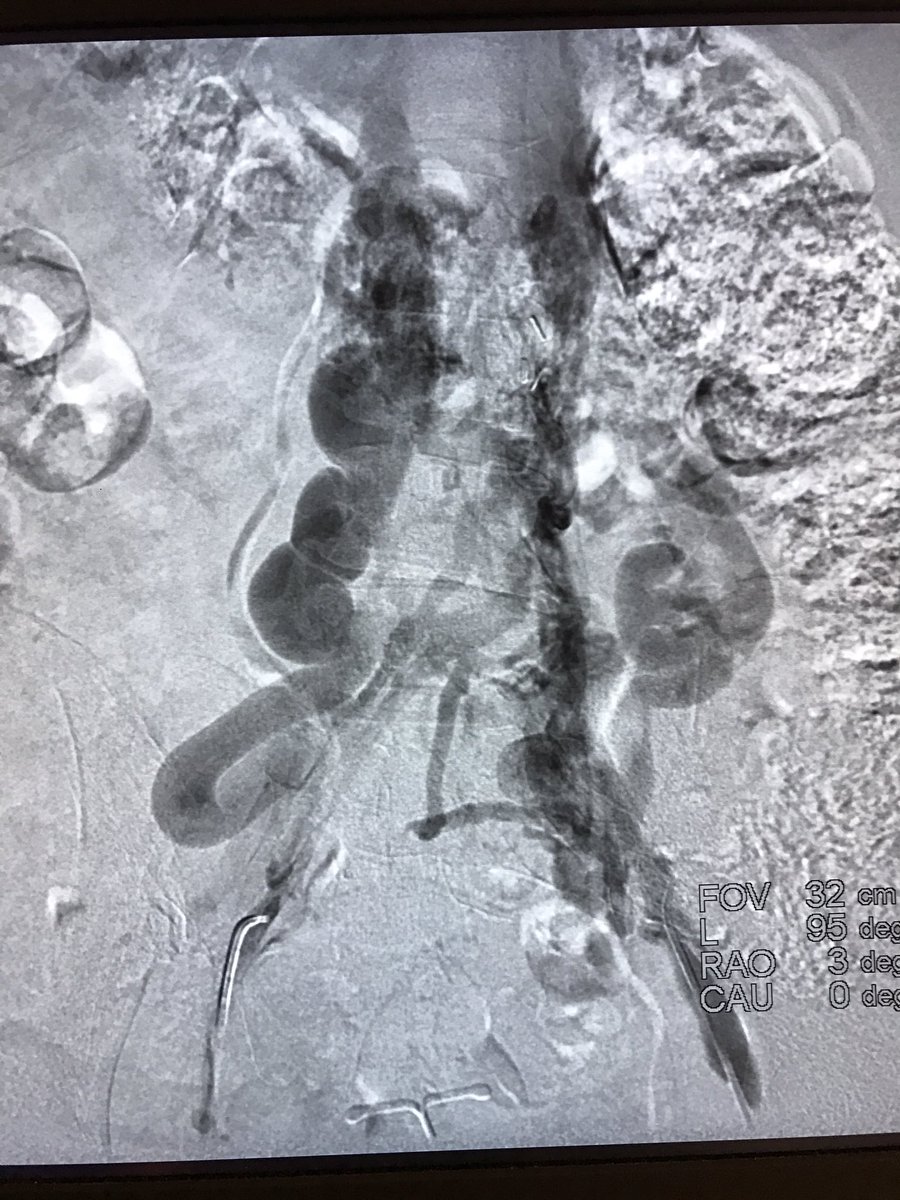

It was hard to say goodbye to this 4 year old filter with strut in the aorta | #iRad #radres #IRmusicvideos #FOAMed #Boyz2men #IRonc